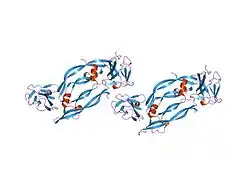

This gene is a member of the platelet-derived growth factor (PDGF)/vascular endothelial growth factor (VEGF) family and encodes a protein that is often found as a disulfide linked homodimer. This protein is a glycosylated mitogen that specifically acts on endothelial cells and has various effects, including mediating increased vascular permeability, inducing angiogenesis, vasculogenesis, and endothelial cell growth, promoting cell migration, and inhibiting apoptosis. Alternatively spliced transcript variants, encoding either freely secreted or cell-associated isoforms, have been characterized.[6]

Vascular endothelial growth factor A (VEGF-A) is a dimeric glycoprotein that plays a significant role in neurons and is considered to be the main, dominant inducer of the growth of blood vessels. VEGFA is essential for adults during organ remodeling and diseases that involve blood vessels, for example, in wound healing, tumor angiogenesis, diabetic retinopathy, and age-related macular degeneration. During early vertebrate development, vasculogenesis occurs which means that the endothelial condense into the blood vessels. The differentiation of endothelial cells is dependent upon the expression of VEGFA and if the expression is abolished then it can result in the death of the embryo. VEGFA is produced by a group of three major isoforms as a result of alternative splicing and if any three isoforms are produced (VEGFA120, VEGFA164, and VEGFA188) then this will not result in vessel defects and death of the full VEGFA knockout in mice. VEGFA is essential in the role of neurons because they too need vascular supply and abolishing the expression of VEGFA from neural progenitors will result in defects of the brain vascularization and neuronal apoptosis. Anti-VEGFA therapy can be used to treat patients with undesirable angiogenesis and vascular leakage in cancer and eye diseases but also could result in the inhibition of neurogenesis and neuroprotection. VEGFA could be used to treat patients with neurodegenerative and neuropathic conditions and also increase vascular permeability which will stop the blood-brain barrier and increase inflammatory cell infiltration.[7][8][9]